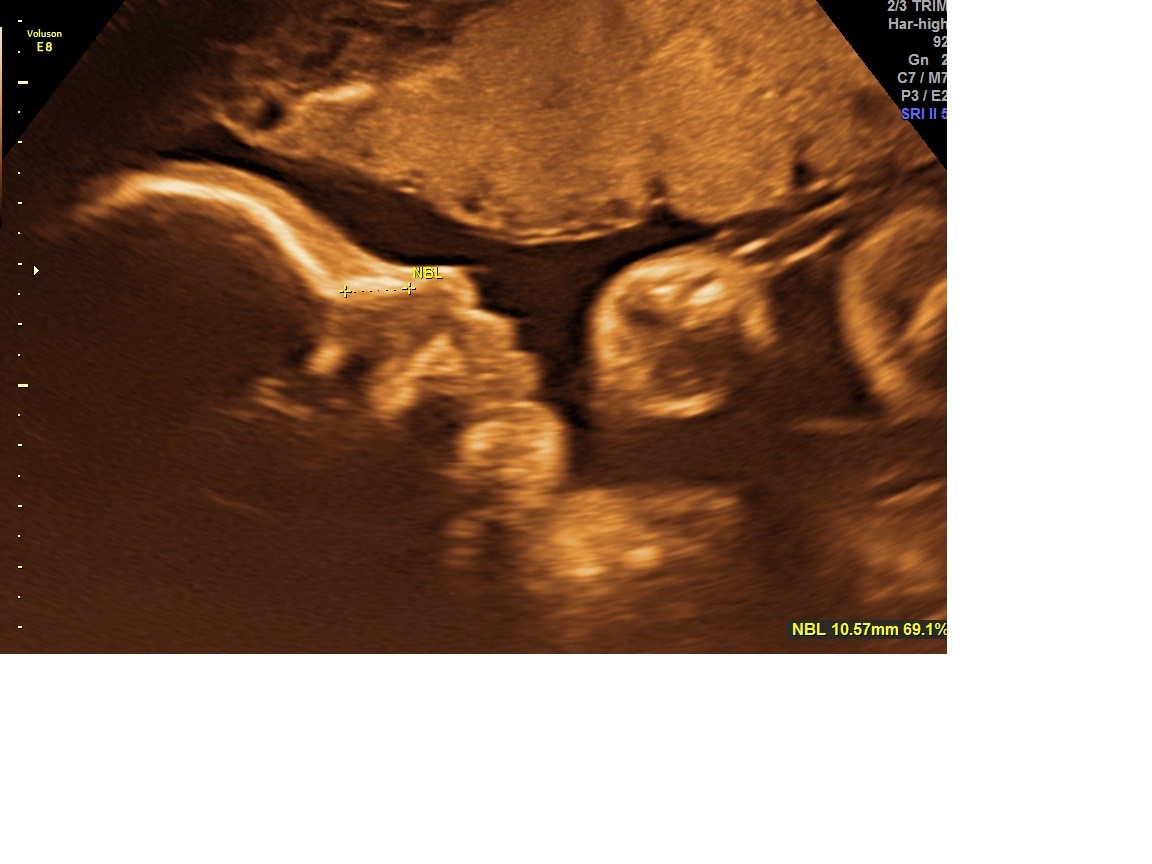

Taką ma buzię cudną :)Zobacz załącznik 774374

Zobacz załącznik 774371 Zobacz załącznik 774370